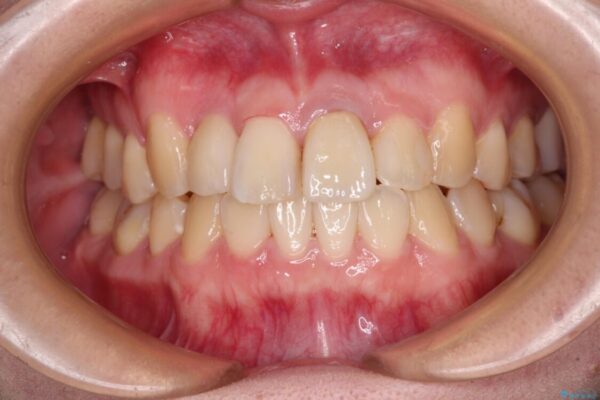

治療後

• 虫歯治療ついでに歯並びの後戻りを改善 インビザラインによる矯正治療 治療後画像